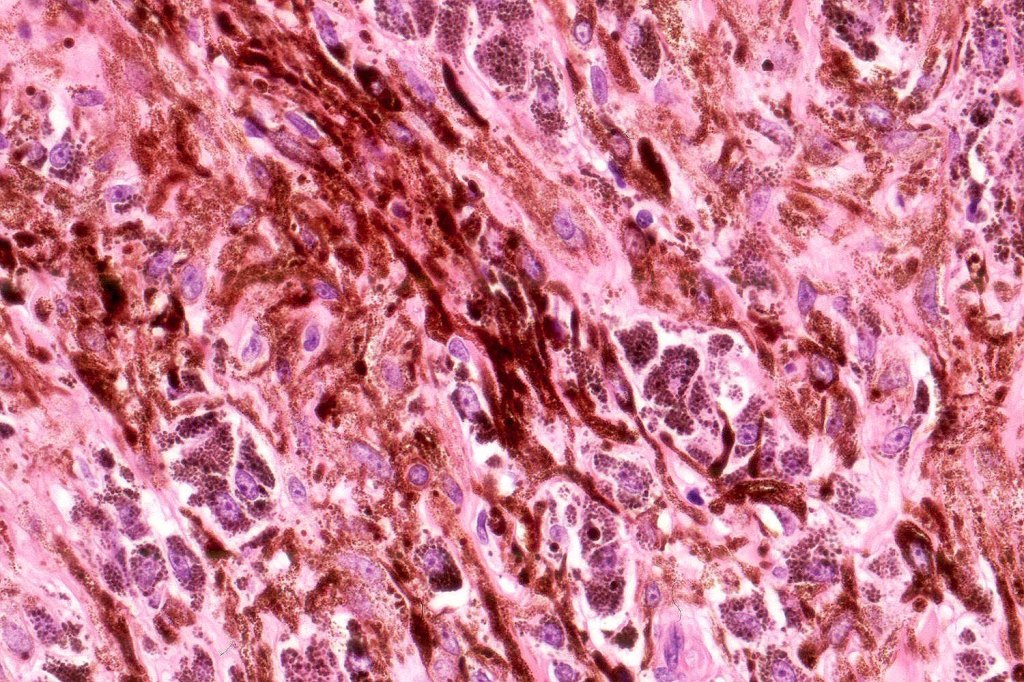

Histologically, it is characterized by a dense population of spindled, dendritic melnanocytes & melanophages with variable fibrosis. It may sometimes represent a component of a combined nevus. Mitotic activity is not usually present and pleomorphism is absent (see atypical blue nevus below). Involvement of the arrector pili muscle is not uncommon.

•Admixture of spindle cells, pigmented bipolar or dendritic cells & melanophages

•An alveolar pattern is characteristic particularly with clear cell nodules